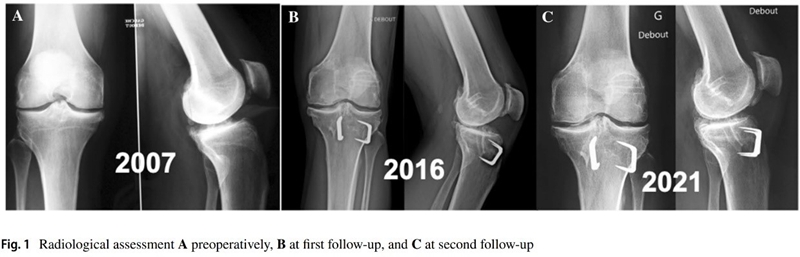

Anouk等人分析ACLR翻修联合胫骨去屈曲截骨术(TDO)的9名患者数据,指出在术后7-15年与术后2-8年随访结果相比,患者的临床评分保持或改善,没有再撕裂或再次手术的情况。证实TDO可以防止ACL移植物再撕裂,在进行ACLR时,无论是翻修还是初次手术,都应考虑矫正过度的胫骨后倾[6]

图4